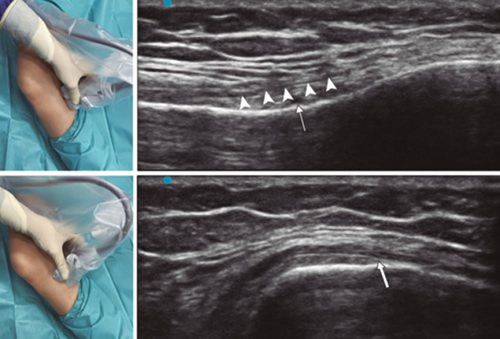

Para lograr una correcta ubicación de las referencias anatómicas por ultrasonido debemos colocar al paciente en posición supina con la rodilla flexionada y una almohada debajo de la fosa poplítea (14,16,19). Después de realizar asepsia/antisepsia de la rodilla, colocación de campos quirúrgicos y de la funda estéril del transductor lineal de alta frecuencia, procedemos a ubicar el NGSM (Figura 3). Colocando la sonda en un plano coronal sobre la cara interna de la rodilla, la deslizamos en sentido craneal hasta visualizar la unión de la metáfisis con la diáfisis femoral y la arteria/nervio geniculado superomedial (ANGSM), usualmente están localizados cerca al periostio del fémur (en caso de no encontrar esta estructura neurovascular, se toma como referencia la unión de la metáfisis y la diáfisis femoral). Después se marca en la piel el punto medio del transductor que corresponde a la ANGSM y se gira el transductor para ubicarlo en el plano transversal o axial para visualizar la ANGSM en eje corto (si no es posible la visualización de esta estructura, confirmar que estamos a un 50 % de la profundidad del fémur). En este corte transversal se avanza la aguja de RFT en plano desde anterior a posterior hacia la ANGSM o hasta una profundidad del 50 % del espesor del fémur. Finalmente se vuelve a girar el transductor 90°, dejándolo en un plano coronal para comprobar que la punta de la aguja está cerca de la ANGSM o de la unión de la metáfisis y la diáfisis femoral (14,16,19).

Fig. 3. Sonoanatomía y técnica para realizar el bloqueo del nervio geniculado superomedial (NGSM). El transductor se ubica en el eje largo distal del fémur y una vez que se tenga la posición del NGSM (asteriscos), se gira la sonda 90 grados para obtener una visión en eje corto del fémur (no olvidar mantener la misma profundidad a la que encontramos el NGSM en el eje largo). VM: vasto medial.

Para ubicar al NGIM (Figura 4) colocamos el transductor en un plano coronal sobre la cara interna de la rodilla, lo deslizamos en sentido caudal hasta identificar la unión de diáfisis con la metáfisis tibial y la arteria/nervio geniculado inferomedial (ANGIM), y repetimos los mismos pasos que usamos para el NGSM. En caso de no encontrar la ANGIM, la referencia que se tomará será la profundidad del 50 % del espesor de la tibia (14,16,19).

Fig. 4. Sonoanatomía y técnica para realizar el bloqueo del nervio geniculado inferomedial (NGIM). El transductor se ubica en el eje largo proximal de la tibia e identificamos el paquete vasculonervioso del NGIM (flecha) justo debajo ligamento colateral medial (puntas de flechas). Luego se gira la sonda 90 grados para obtener una visión en eje corto de la tibia (no olvidar mantener la misma profundidad a la que encontramos el NGIM en el eje largo).

Para ubicar el NGSL, el paciente debe estar en posición supina con el miembro inferior en rotación interna, consiguiendo una buena exposición de la cara lateral del muslo. Colocamos el transductor lineal en un plano coronal sobre la cara lateral de la rodilla, lo deslizamos en sentido craneal hasta visualizar la unión de la metáfisis con la diáfisis femoral y la arteria/nervio geniculado superolateral (ANGSL), y repetiremos los mismos pasos que usamos para el NGSM (14,16,19).